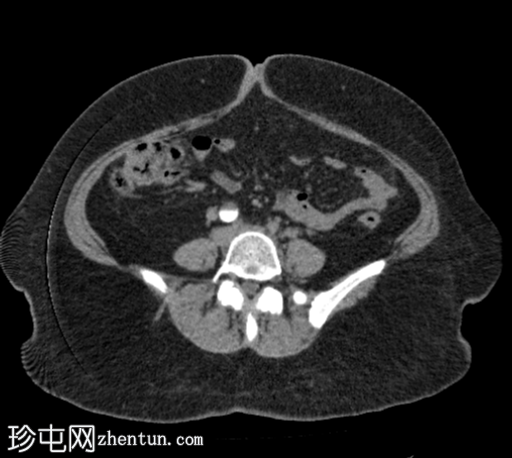

轴位肾皮质期

右肾中度肾积水,输尿管积水延伸至S4椎体水平。延迟期图像显示阴道残端扩张并充满造影剂,与右侧远端输尿管相通。

延迟期图像显示右侧肾盂呈斑片状强化,提示延迟性肾图,可能由远端梗阻引起。